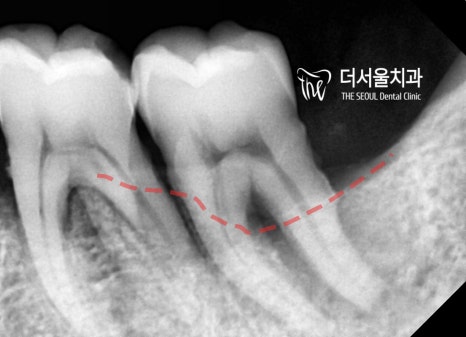

우측사진에서는 치조골 염증에 따른 치조골의

퇴축 현상이 명확하게 드러납니다.